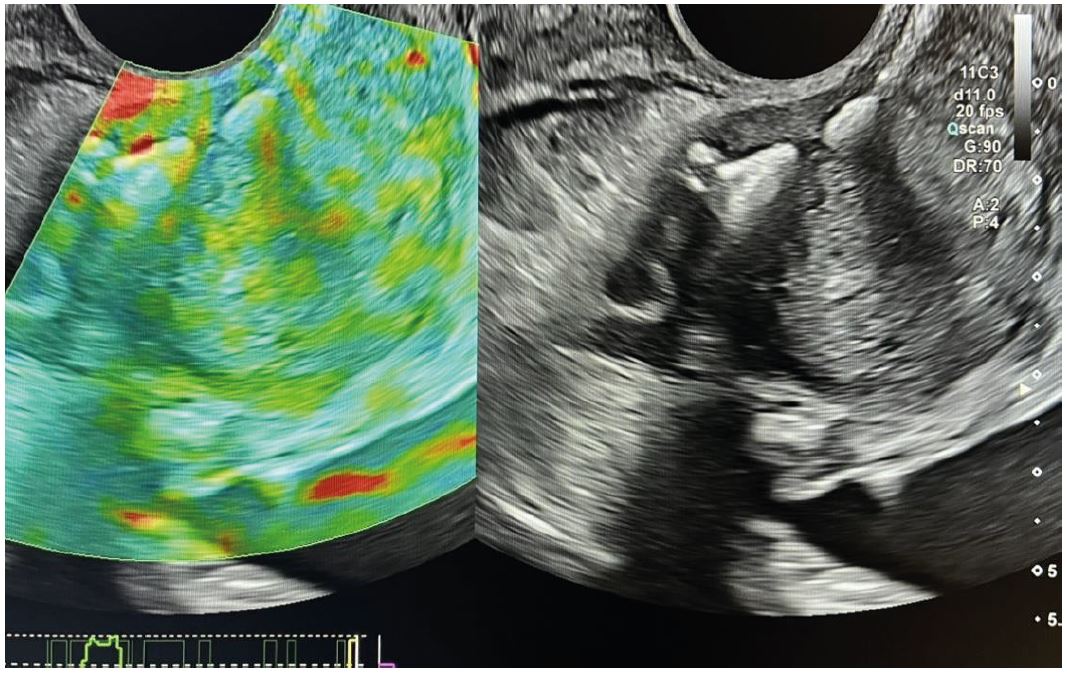

Значення ПСА вище вказаних значень до 10 нг/мл прийнято позначати «сірою зоною», коли важко визначити показання до проведення біопсії ПЗ. Значення ПСА вище 10 нг/мл є основою проведення біопсії ПЗ. Хворому була виконана трансректальна поліфокальна біопсія ПЗ під мультипараметричною (мп) ультразвуковою навігацією та ехоконтрастуванням Соновью (рис. 1 - 5).

Рис. 1. Якісна еластографія.